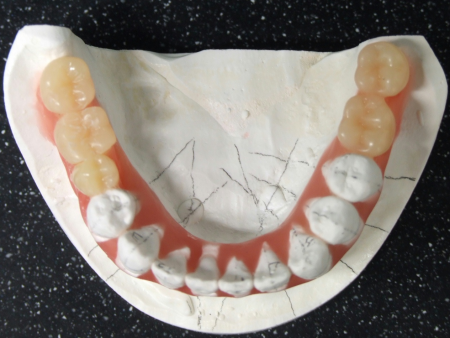

したがって右下前歯を動かさない計画のもと右下前歯の位置を基準としてそれ以外の歯を並べ直して理想的な歯並び、噛み合わせを再現した「セットアップ模型」を製作しました。

セットアップ模型:患者様の歯型をもとに作製した模型の歯の部分を切りだしてバラバラにしてから理想的な位置に並べ直して、咬合治療のゴールをシミュレーションし、確認するために用います。

このセットアップ模型を計測することでインプラントを埋入しなければならない正しい位置を知ることができます。

下の奥歯4本(右第2小臼歯、左第1大臼歯、左右第2大臼歯)には、シミュレーションで決定した位置に正確にインプラントを埋入しました。

次に、左上のブリッジの土台歯だった2本(犬歯、第2小臼歯)とインプラントを埋め込んだ4本それぞれに仮歯を装着したあと、上下すべての歯の表側に矯正装置を装着します。